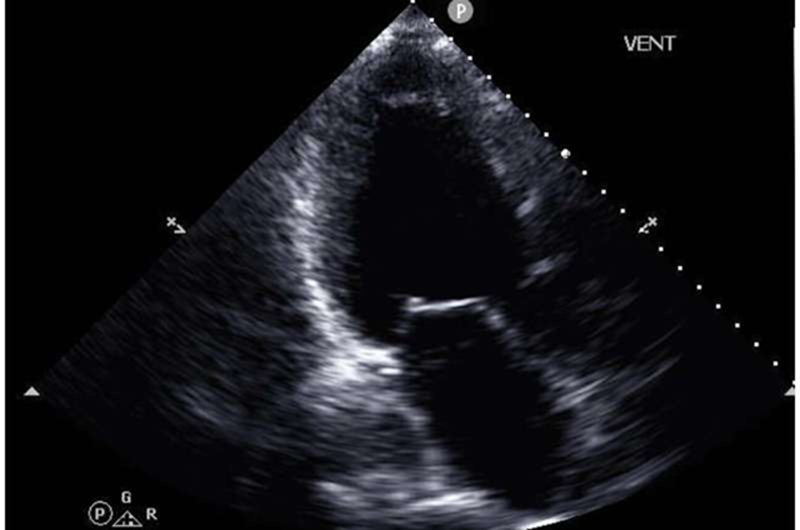

Trong nghiên cứu mới , được công bố tạp chí npj Digital Medicine , các nhà nghiên cứu đã thử nghiệm một phương pháp mới dựa trên trí tuệ nhân tạo (AI) có thể loại bỏ nút thắt cổ chai này. Phương pháp mới này dự đoán với độ chính xác cao chỉ số quan trọng nhất của CPET, mức tiêu thụ oxy tối đa (peak VO2 ) , bằng cách sử dụng hình ảnh siêu âm tim của bệnh nhân dễ thu được hơn nhiều, cùng với hồ sơ sức khỏe điện tử của bệnh nhân.

Nhóm nghiên cứu AI do Tiến sĩ Wang dẫn đầu, bao gồm các tác giả chính Tiến sĩ Zhe Huang và Tiến sĩ Weishen Pan cùng với các sinh viên và giảng viên tại Cornell Bowers, đã phát triển một mô hình học máy đa phương thức, đa trường hợp có thể xử lý nhiều loại dữ liệu khác nhau, bao gồm hình ảnh siêu âm chuyển động thông thường của tim, hình ảnh dạng sóng liên quan hiển thị động lực van tim và lưu lượng máu, và nhiều mục khác nhau được tìm thấy trong hồ sơ sức khỏe điện tử.